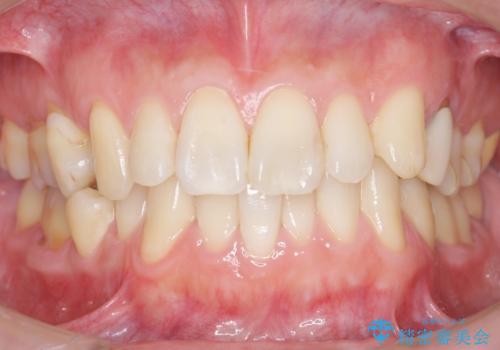

内側に生えている歯をなんとかしたい 矯正は嫌 30代男性

- 下の奥歯が内側に生えていることを主訴に来院された患者様です。

精査したところ、左下の小臼歯(左下5)が舌側転位しており、また隣の歯の詰め物は欠け虫歯になっていました。

矯正は絶対にしたくないという強いご希望により、舌側転位している歯を抜去し歯肉の治癒を待ったのち、両隣の歯の補綴治療を行いました。

セラミッククラウンにより、抜歯した部分のスペースを閉じ歯並びを整えました。

矯正装置を用いることなくセラミッククラウンにより歯並びを整えスペースを閉じることができ、大変ご満足頂けました。